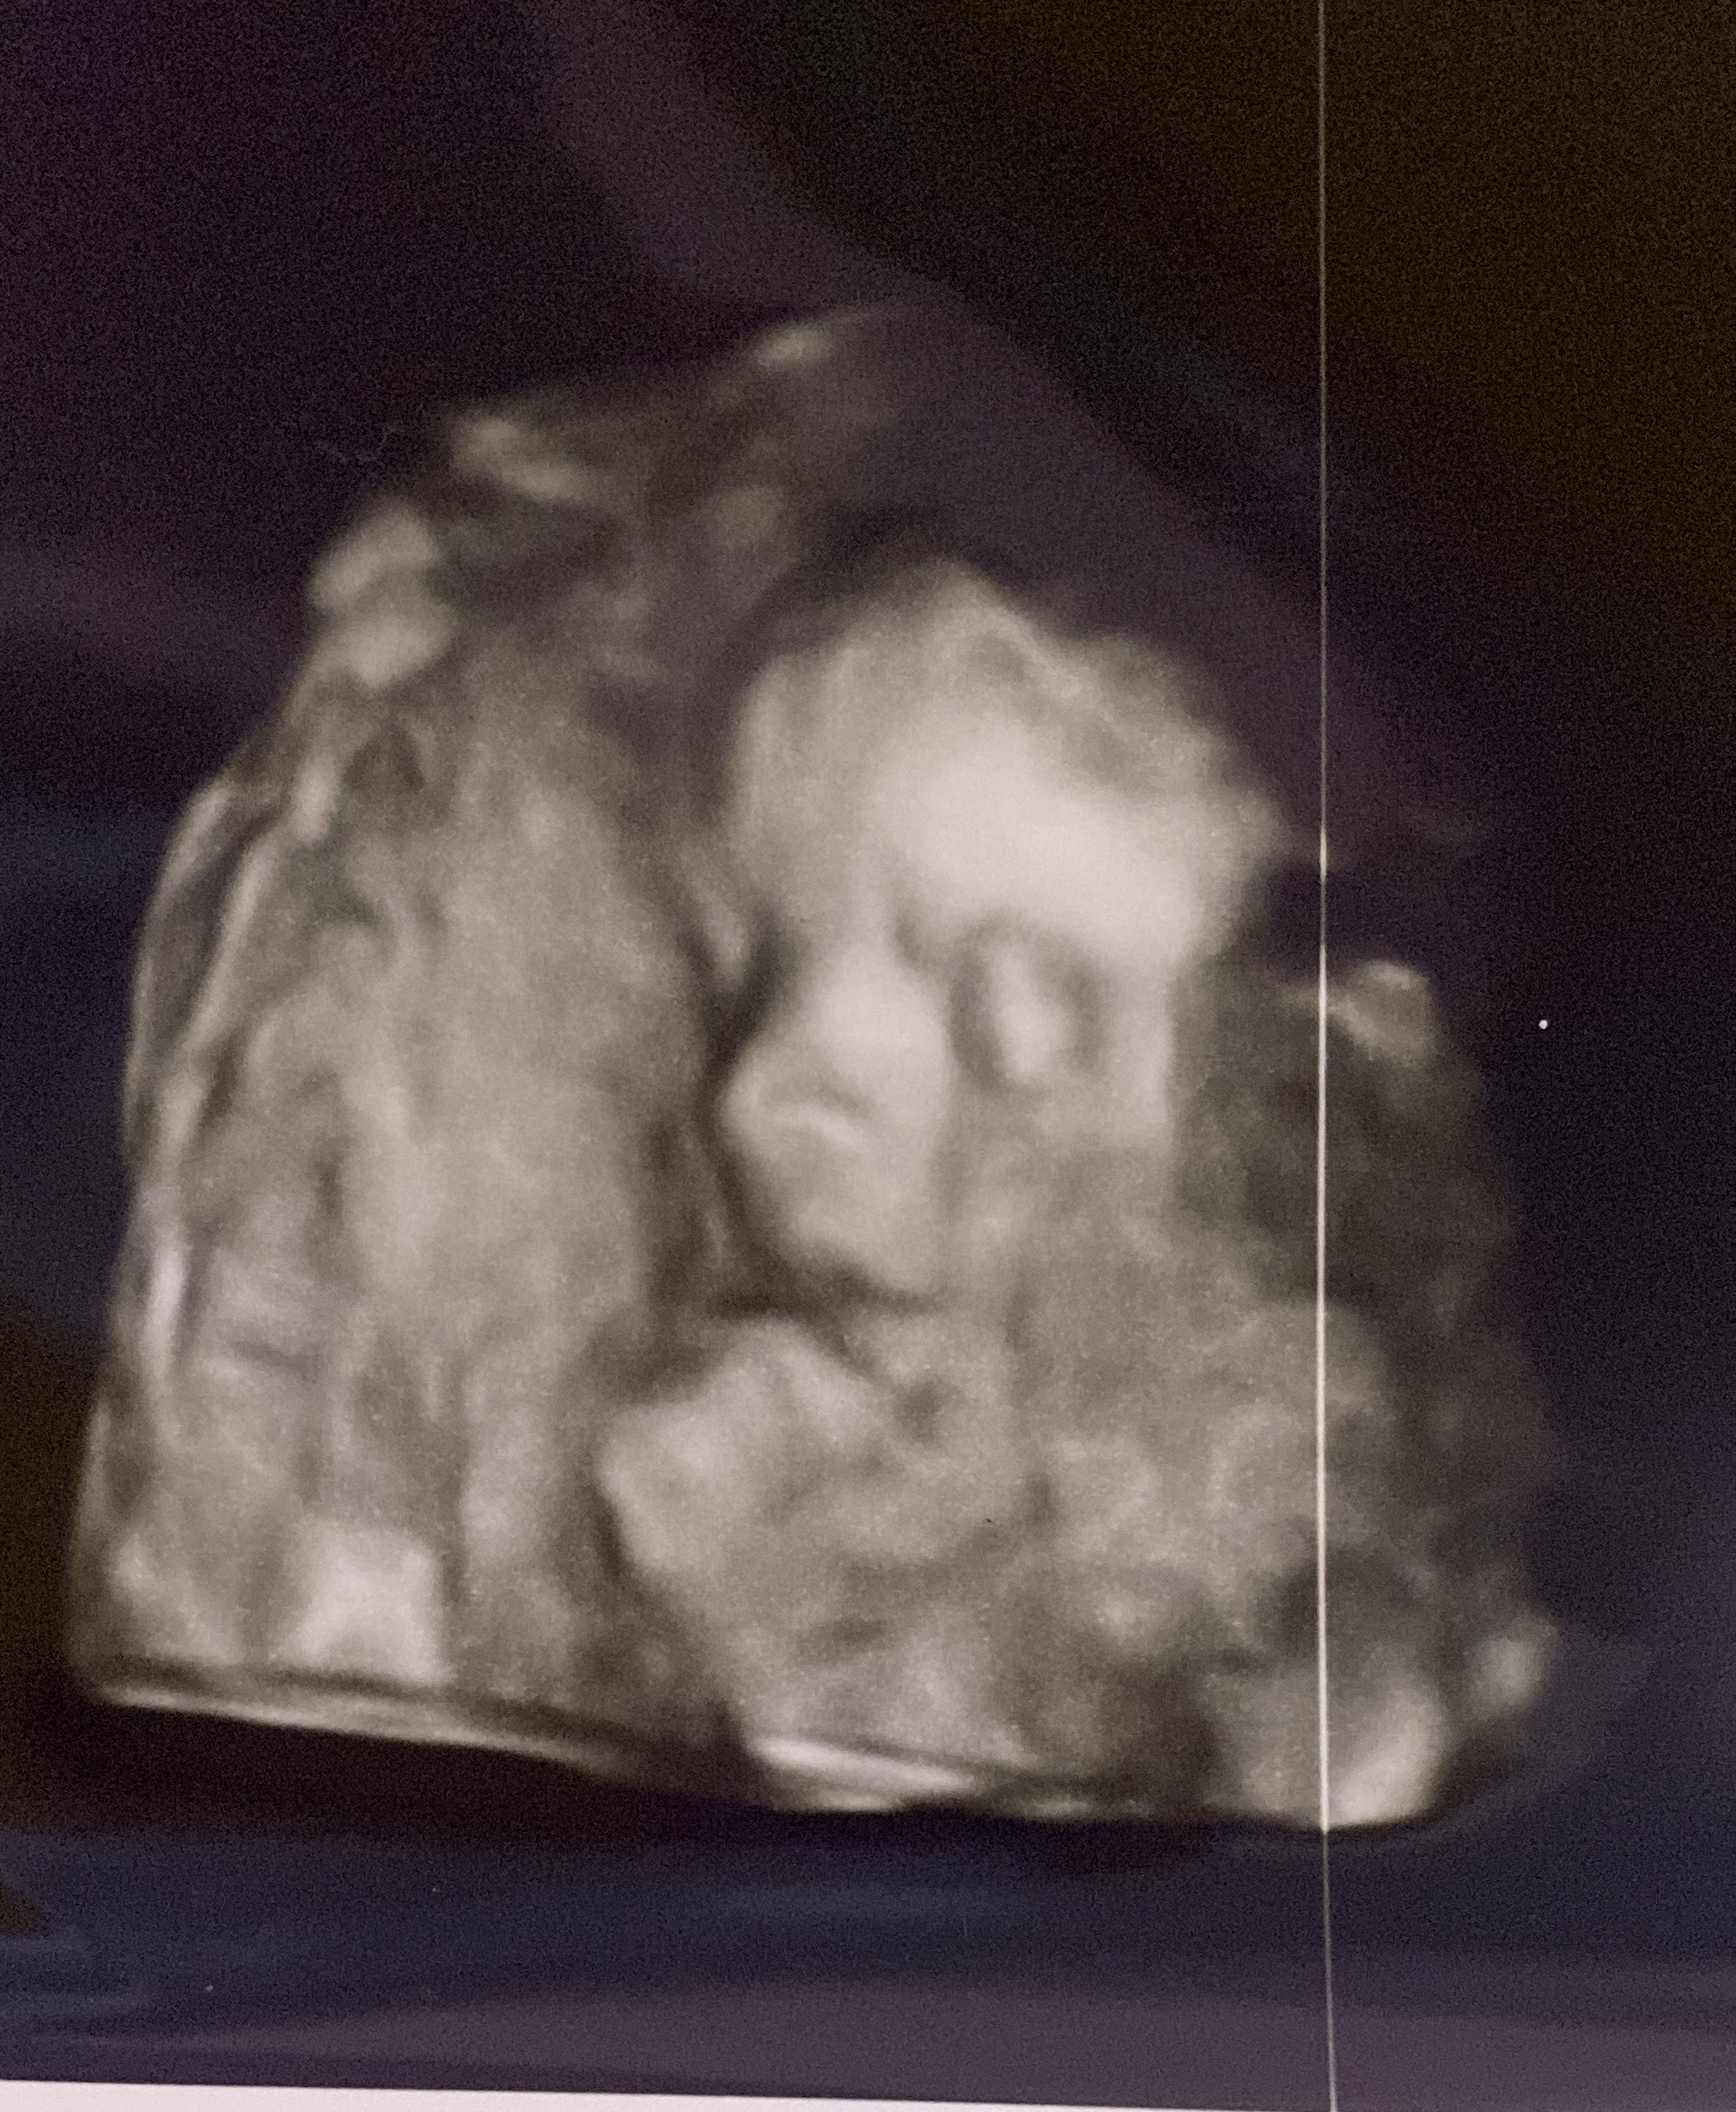

Pochwale się moją pociechą z dziś 🥹 urocze zdjęcie jak malutka ssie kciuka 🥰

https://zapodaj.net/plik-7tl0VxM9RE

Lila777 ale słodka ta Twoja córcia 🥹 super, że udało im się tak uchwycić zdjęcie!